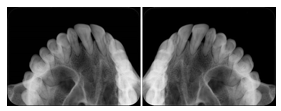

3. A patient in rural Minnesota experiences sudden vision loss and goes to a general ophthalmologist, who acquires OCT images and forwards them electronically along with a Structured Display to a retina specialist six travel hours away. The retina specialist is able to view the images in the standard layout that he is comfortable with, and to confirm that the patient has a choroidal neovascular membrane. He determines that is would be worthwhile for the patient to travel for treatment.

OCT Retinal Study with Cross Section and Navigation Structured Display

Figure OO-4. OCT Retinal Study with Cross Section and Navigation Structured Display